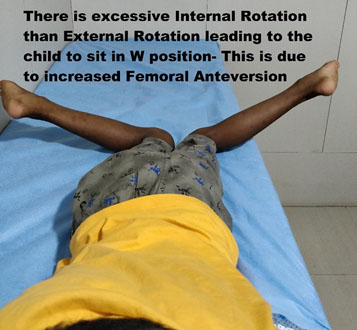

FEMORAL ANTEVERSION (FNA)

FNA is a condition where the intoeing is because of excessive forward pointing of the neck of the femur with respect to the knee joint line (the angle formed between the coronal plane and the neck of femur is called as ante-version. Most often, this condition presents in kids between 2-8 years of age and is equal in both the sexes. It manifests as excessive inward-pointing of the toes, especially when the child is tired, running. Parent’s complaint that the child sits in W position or reverse tailor position. The best way to examine this is to put the child prone and measure the amount of internal rotation (IR) and compare it to the opposite hip. In a prone patient, hip rotation outside is an internal rotation of the hip, and the reverse direction is External rotation.